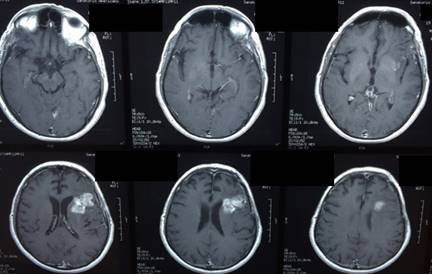

Figura 6: Oligodendroglioma grado II. Resonancia Magnética corte axial. Arriba a la izquierda se ve una extensa lesión frontal derecha con importante efecto de masa. Se realizó una primera cirugía con anestesia general, haciendo una resección amplia y posteriormente se planificó una cirugía con despertar para ampliar el margen. Arriba a la derecha se ve el lecho con líquido y material hemostático, abajo el lecho quirúrgico evolucionado con una resección subtotal (mínimo remanente en el cuerpo calloso).